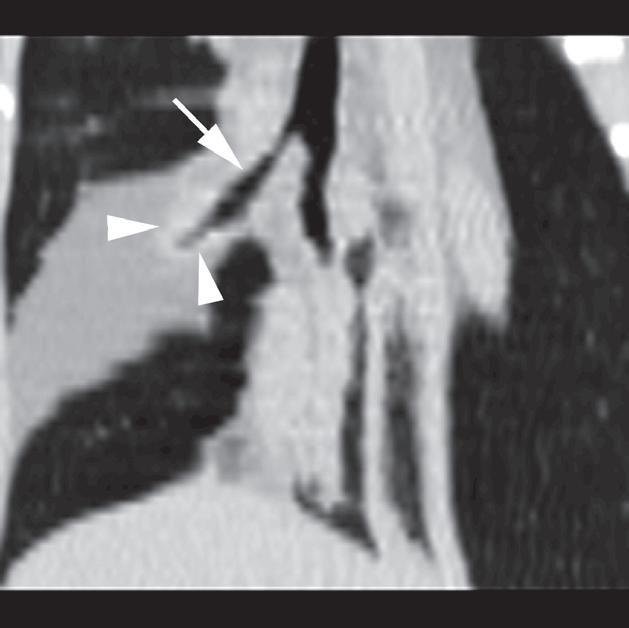

Rycina 4.1.3. Ciało obce penetrujące ścianę klatki piersiowej (pies) TK

Badanie wykonano u 5-letniej, kastrowanej samicy mieszańca pointera, u której 5 miesięcy przed badaniem wystąpił nagły epizod kaszlu podczas spaceru. Właściciele zauważyli wówczas małą otwartą ranę w ścianie klatki piersiowej. Obecnie od 5 dni u psa występują duszności. Na zdjęciach rentgenowskich widoczne jest krótkie, linijne zacienienie o atenuacji zbliżonej do tkanek miękkich, znajdujące się w rejonie lewego doogonowego płata płuc (a – grot strzałki). Na poprzecznych obrazach TK uwidoczniono linijne ciało obce o atenuacji miękkotkankowej (b – strzałka) oraz niewielką odmę opłucnową (b – grot strzałki). Całkowitą długość ciała obcego można najlepiej ocenić na obrazie MIP zorientowanym w płaszczyźnie poprzecznej (c – groty strzałek). Ciało obce usunięto poprzez torakotomię (d – strzałka) i ustalono, że był to pręt z włókna węglowego lub plastiku, na który pies nadział się 5 miesięcy wcześniej